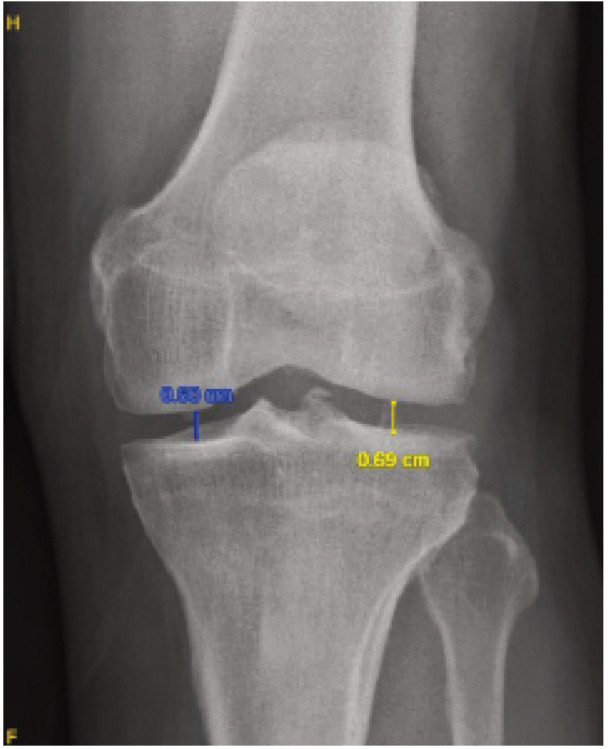

Materials and methods: A prospective cohort study on patients with knee osteoarthritis receiving treatment in a single tertiary hospital was conducted. All patients consented to participate in this study. Patients were assessed functionally with the Western Ontario and McMaster Universities Osteoarthritis Index (WOMAC) and radiologically with plain radiographs. Patients were subjected to undergo both supine and standing plain radiographs of the knee in the same setting for comparison purposes where measurement is done following patient functional outcome and radiological measurement for the patient.

Results: Our study shows that reduction in joint space is more obvious in weight-bearing radiographs, however in severe or higher-grade osteoarthritis, a supine radiograph is adequate to diagnose knee osteoarthritis.